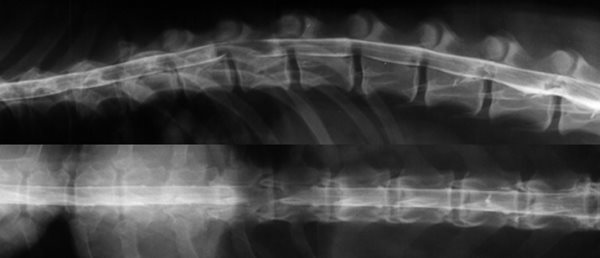

La myélographie.

C'était l'examen de choix jusqu'à ces dernières années pour le diagnostic des hernies discales, le développement du scanner tend actuellement à le supplanter.

Il s'agit d'un examen radiologique sous anesthésie. Un produit de contraste iodé radio-opaque est injecté dans l'espace sous arachnoïdien. Des clichés sont alors effectués pour mettre en évidence des déviations de la moelle épinière ou des modifications de la prise du liquide de contraste.

Myélographie Hernie Discale T12-T13

La myélographie est souvent suffisante pour établir un diagnostic et poser l'indication chirurgicale, cependant dans certains cas, en présence d'un gros oedème médullaire ou de difficultés de latéralisation, il peut être nécessaire d'avoir recours à des moyens d'imagerie tridimensionnels comme le scanner ou l'IRM.

Les imprécisions liées au caractère bidimensionnel de l'examen le rend actuellement obsolète face à la tomodensitométrie numérisée. Son usage peut encore se justifier en situation d'urgence neurologique chirurgicale et en l'absence de disponibilité d'un scanner. La myélographie, avec ses carences, demeure un examen utile, tant par sa simplicité de réalisation que par sa grande accessibilité matérielle (un simple appareil de radiologie permet d'y avoir recours).